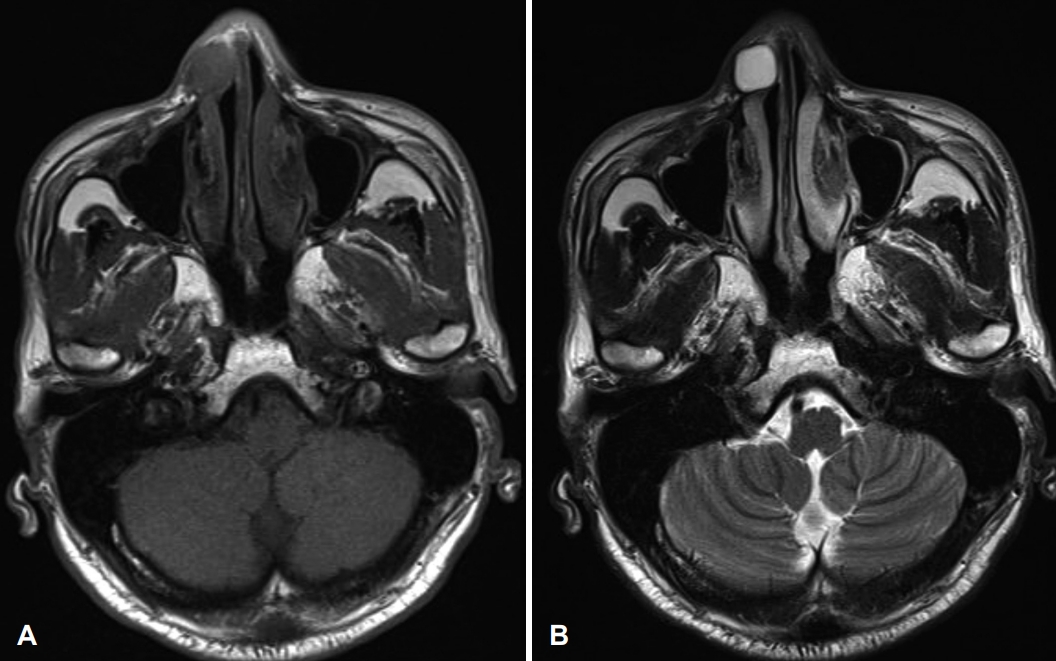

CaseA 58-year-old male patient visited our hospital with a right nasal dorsum swelling. CT scan demonstrated a 1.3×0.5 cm poorly enhanced low attenuation lesion in right nasal ala (Fig. 1). Fine-needle aspiration cytology tests confirmed benign myxoid spindle cell lesions. Surgery was recommended, but the patient refused the operation. Five years later, the patient returned to the hospital because the swelling of the right nose worsened (Fig. 2). MRI demonstrated a 1.7×1.3×1.2 cm T1-weighted image low signal intensity, T2-weighted image high signal intensity, and peripheral enhanced soft tissue lesion in right nasal ala (Fig. 3).

Radiographically, myxomas are usually well-defined ovoid masses with bony destruction or remodeling that show attenuation similar to that of water on CT [2]. On MRI, the tumor exhibits the signal intensity characteristic of fluid [6]. Intraoperatively, most masses are usually identified as glistering gelatinous masses which are oval or spherical in shape [2,4,7]. Histologic features of myxoma include spindled and stellate cells embedded in a fibromyxoid background [2,5,7,8]. Therefore, the definitive diagnosis of myxoma is made by microscopic examination to identify bland spindle cell myxoid lesion [2-6]. The spindled cells of myxoma will stain positively for vimentin and may show some positivity for S-100 protein and muscle-specific actin [2].

NotesAuthor Contribution Conceptualization: Dong Hoon Lee. Data curation: Bong-Jin Shin, Keon Woo Park, Dong Hoon Lee. Formal analysis: Dong Hoon Lee. Investigation: Dong Hoon Lee. Supervision: Sang Chul Lim. Validation: all authors. Writing-original draft: Bong-Jin Shin, Dong Hoon Lee. Writing-review & editing: all authors. Fig. 3.A 1.7×1.3×1.2 cm T1-weighted image (A) low signal intensity, T2-weighted image (B) high signal intensity, peripheral enhanced soft tissue lesion in right nasal ala. REFERENCES1. Virchow R. Die Cellularpathologie in ihrer Begründung auf physiologische und pathologische Gewebelehre. Berlin: Verlag van August Hirschwald; 1871. p. 563.